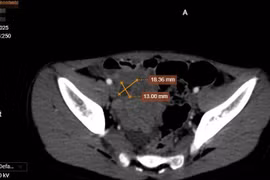

Đau bụng, bí tiểu người bệnh 47 tuổi không ngờ bị u xơ tử cung hiếm gặp

Chị em phụ nữ nên thường xuyên khám phụ khoa định kỳ, đặc biệt từ tuổi trung niên trở lên kể cả khi không có triệu chứng bất thường.